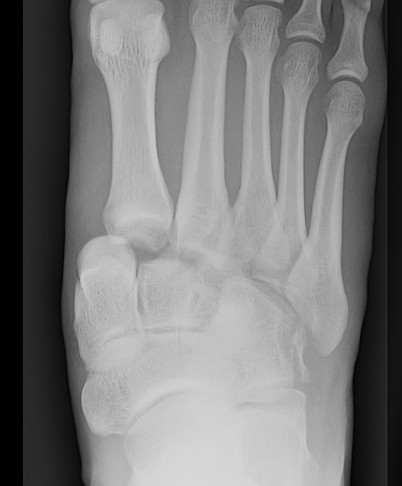

1. Diastasis of the intermetatarsal gap between the 1st and 2nd metatarsals

2. Widening of the space between the medial cuneiform and base of 2nd metatarsal

3. Second metatarsal Fleck sign - avulsion of Lisfranc ligament from base of 2nd metatarsal

4. Widening of inter-cuneiform distance

5. Dorsal subluxation of the metatarsals

6. Tarsometatarsal alignment disruption

- medial border 1st metatarsal aligns with medial border medial cuneirform (AP foot)

- medial border 2nd metatarsal aligns with medial border middle cuneiform (AP foot)

- medial border 3rd metatarsal aligns with medial border lateral cuneiform (AP view)

- medial border 4th metatarsal aligns with medial border of the cuboid (oblique view)

X-ray

AP / Assess medial column

Internal Oblique 30o / Assess lateral column

Lateral / assess dorsal displacement